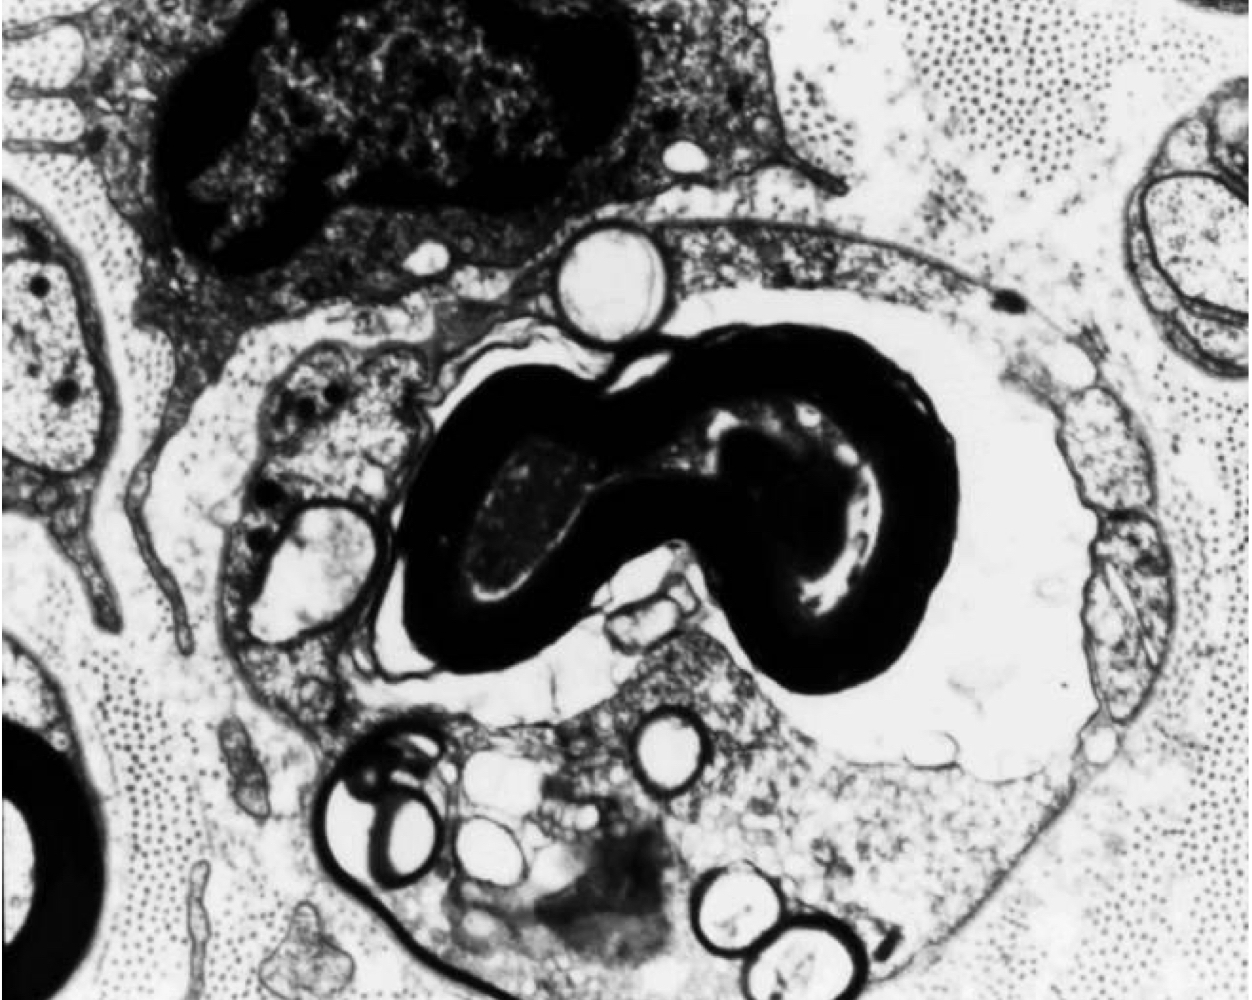

16

• granulomatous polyradiculoneuritis

• thickened nerve roots with inflammatory cells

Q

• thick nerve roots

• non-suppurative, granulomatous inflammation